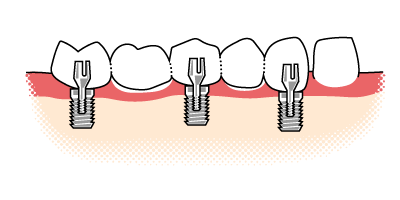

Implantatbrücke